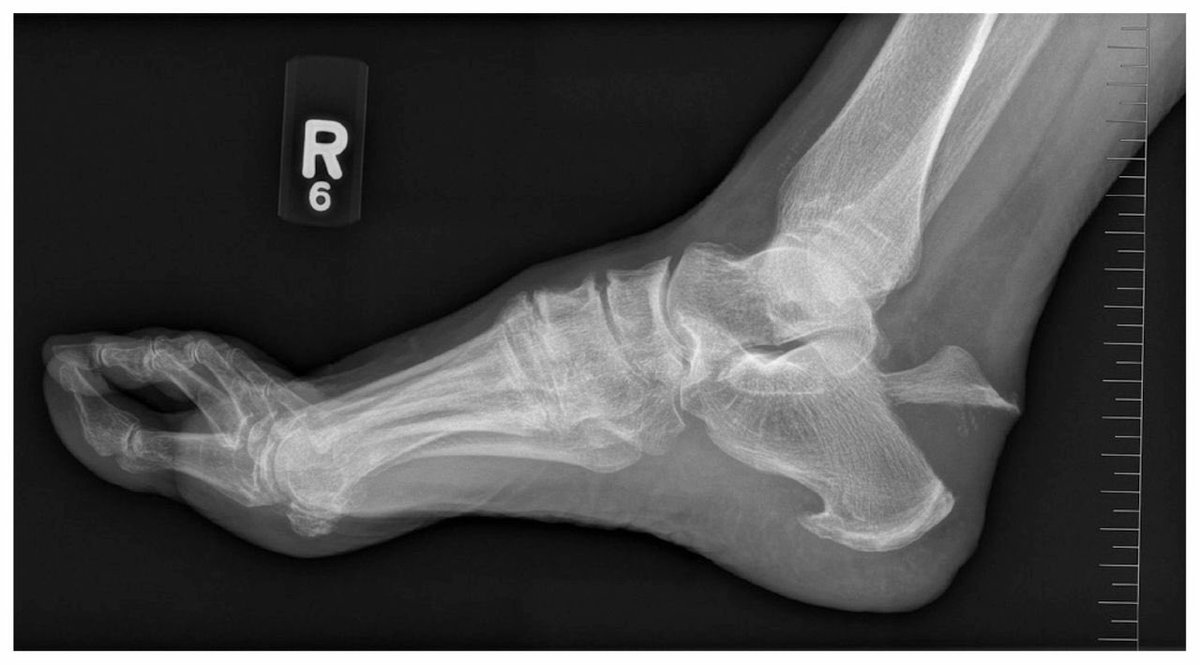

طيب نجي للتشخيص !

الاشعه

يوضح بهذا الشكل